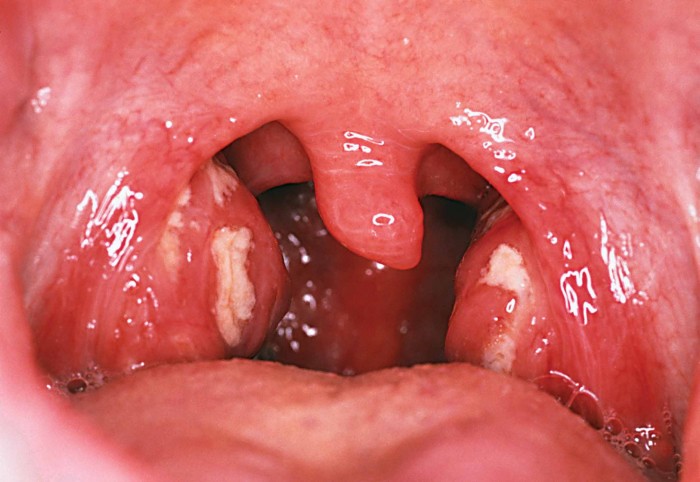

При первинному огляді лікар може помітити сильне почервоніння і запалення мигдалин. Дуже часто захворювання супроводжується наявністю гнійників на гландах, а при обмацуванні можна виявити ущільнення і запалення лімфовузлів.

Якщо ангіна протікає в гострій формі, то мигдалики виглядають запаленими і повністю покриті гнійним вмістом, яке може поширюватися і на сусідні області. В залежності від того, які симптоми і лікування підбирається відповідне, так як хвороба може протікати в різних формах.

Під час огляду ЛОР виявляє такі ознаки хронічного тонзиліту:

- Мигдалини зростаються з піднебінними дужками.

- У лакунах утворені гнійні пробки, які містять лейкоцити, слиз і продукти життєдіяльності бактерій.

- Структурна зміна анатомії мигдалин.

- Почервоніння і набряк мигдаликів.

Також додаткову інформацію дає огляд самого горла і безпосередньо гланд. Їхній обсяг зростає, поверхня стає рихлою, слизова оболонка червоніє, при певних видах тонзиліту на її поверхні з’являються точкові жовто-білі освіти або гнійний наліт.